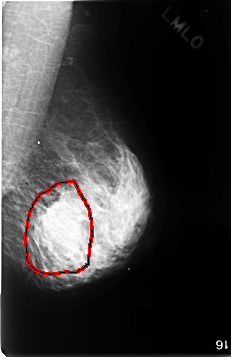

FILE: C_0343_1.LEFT_MLO.OVERLAY

TOTAL_ABNORMALITIES 1

ABNORMALITY 1

LESION_TYPE MASS SHAPE LOBULATED MARGINS ILL_DEFINED

ASSESSMENT 5

SUBTLETY 4

PATHOLOGY MALIGNANT

TOTAL_OUTLINES 1

BOUNDARY